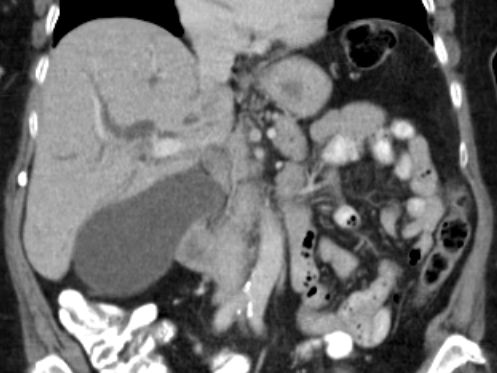

| Cholestase | 78-jährige Frau mit Pankreaskopfkarzinom. Die intrahepatischen Gallenwege sind stark erweitert.![]() |

Gallenblasenhydrops. Die kontrastierten Leberarterien verlaufen parallel zu den Gallenwegen.![]() |